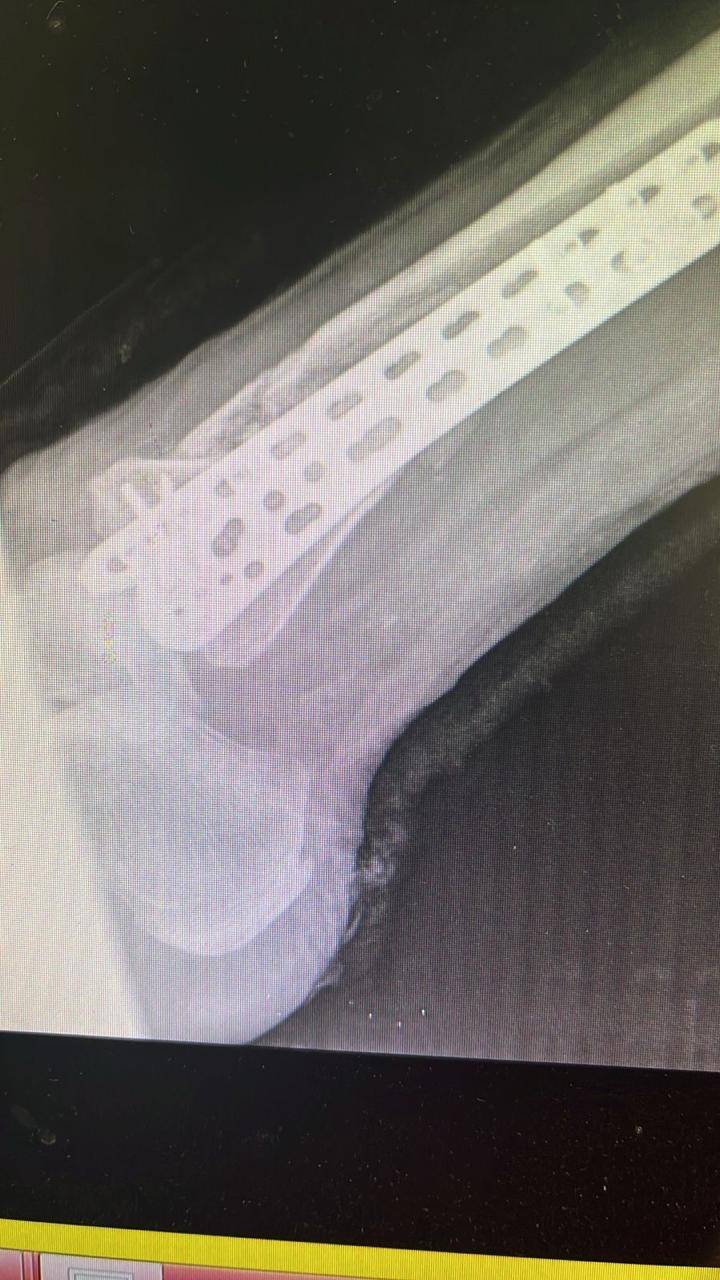

- إجراء عمليات جراحية معقدة و دقيقة في مجال العظام و المفاصل و الكسور و الإصابات ، رغم الضغط الكبير على المستشفى و أعداد المراجعين الكبيرة.

- تطبيق تقنيات جراحية حديثة و متقدمة، و ذلك في ظل التحديات التي يواجهها الفريق بسبب أعداد المرضى و المراجعين الكبيرة.